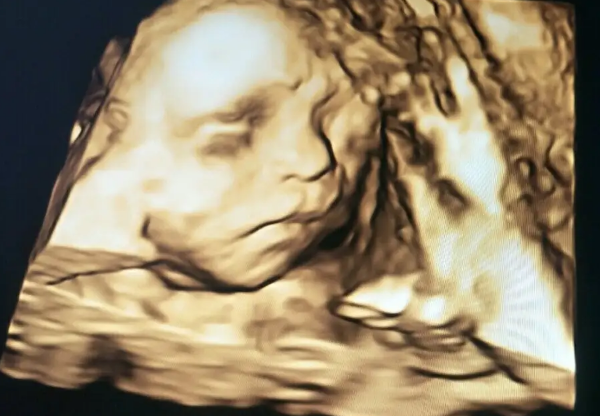

在怀孕中期有一个特别特殊的时间,就是怀孕6个月,24周左右,24周胎儿在子宫里的发育可以说是一个奇妙的过程,这个阶段的胎儿开始具有更多的自主性,他们的五官发育也已经完成,但身体的其他部分还处在不断地发育之中,每一天都在发生着微小的变化,为了帮助大家进一步了解24周胎儿的实际情况,接下来就通过24周胎儿在子宫中的图片,分析一下具体特征:

3、胎儿面貌可辨认:如果孕妇在怀孕24周去医院做四维彩超,运气好的话就能观察到胎儿的五官特点,它的身体系统正在形成。它的眼睛也经历了很大的变化,它可以看到轮廓清楚的物体,而且眼睛可以移动,它可以看到子宫内的光线。